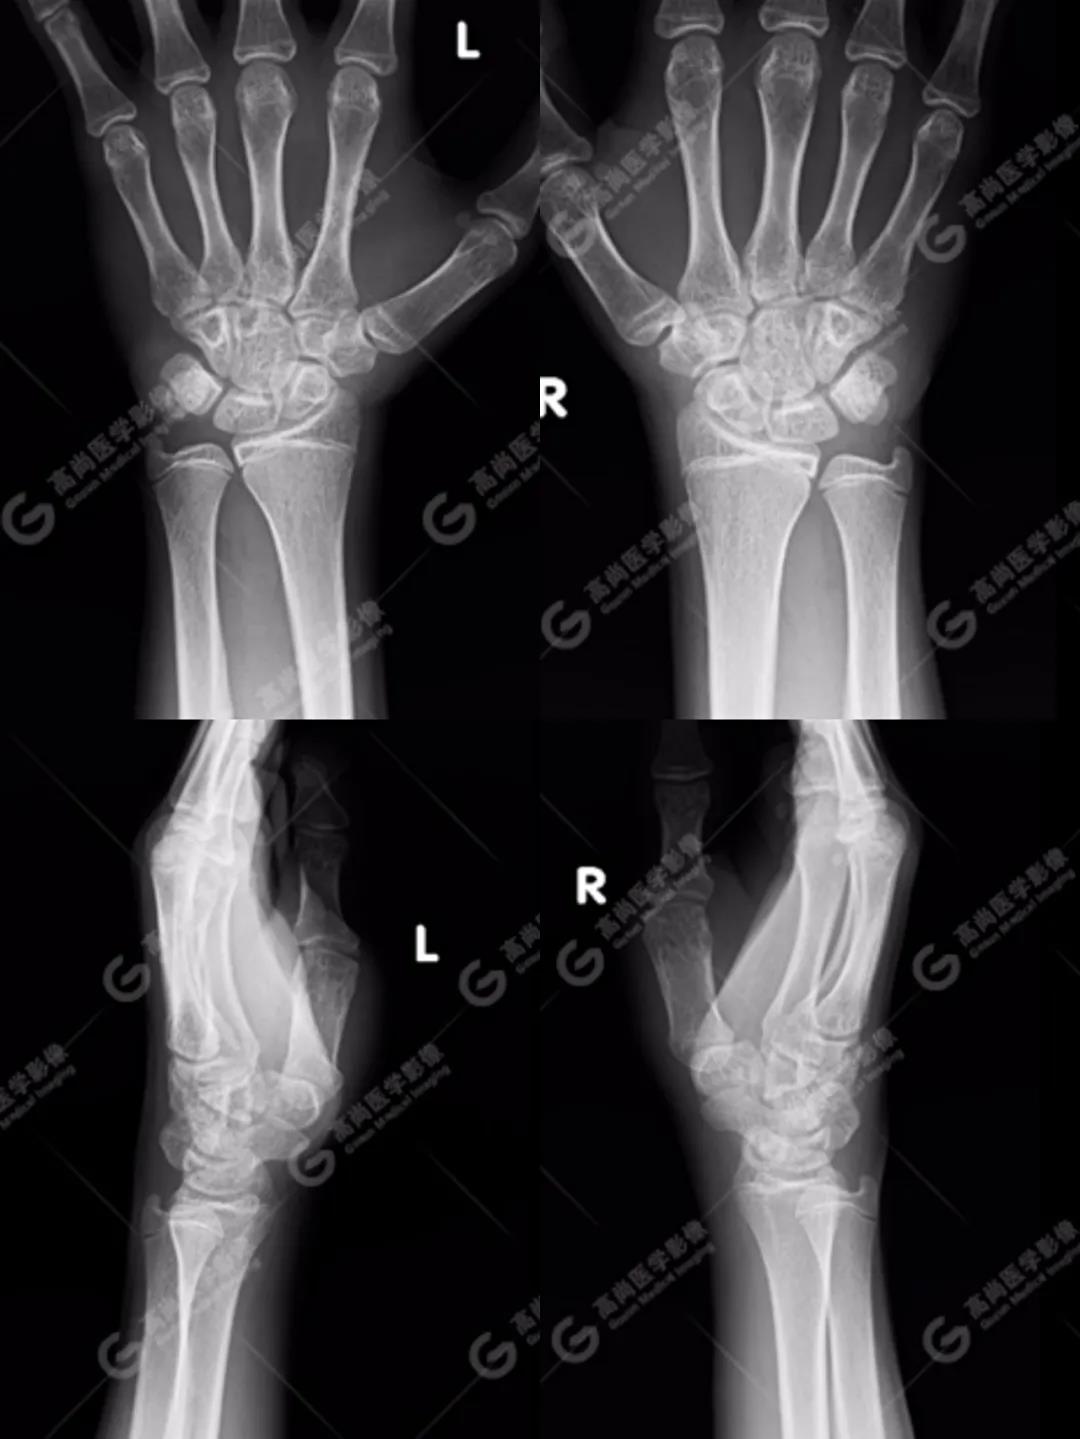

1、雙腕關節(jié)正側位平片

按照臨床診療的常規(guī)思路,遇到這種情況首先行X線平片攝影檢查(老百姓通俗講的“照片”)。

如下圖所見:雙腕關節(jié)諸骨未見明顯骨折征象。

沒有看到明顯的骨折線,患者的疼痛是不是軟組織損傷造成的、回家擦一些紅花油之類的外用藥就ok了的“小問題”呢?考慮到孩子即將面臨考試,家長還是不放心,擔心X線影像重疊等因素造成漏診,想進一步明確,提出進行CT檢查(由于成像原理的差別,CT對于細微骨折的顯示要明顯優(yōu)于常規(guī)X線攝影)。